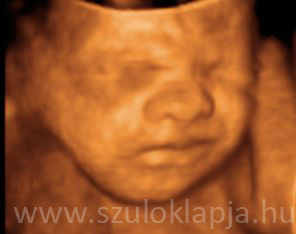

Már az anyaméhben látnak a babák

A vizsgálatok tanúsága szerint a megszületett kisbabák remekül tudnak fókuszálni 20-30 centire.

Miért ennyire és hol tanulták?

A méhen belül a szemhéjak zárva vannak a 26. hétig, hogy a retina teljes mértékben ki tudjon fejlődni. Attól kezdve, hogy a szemek kinyílnak a látás is megjelenik valami módon. Kísérletek igazolják, hogy az anya hasának erős fénnyel való megvilágításakor a magzat szívverése megváltozik.

UH fotók: Beleznay Katalin